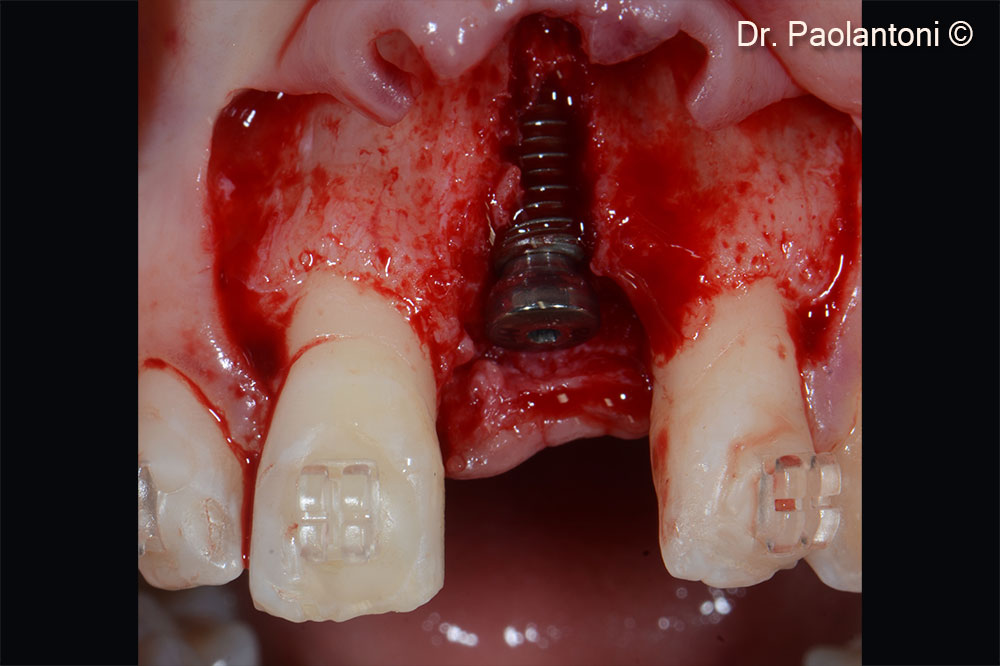

Implant positioning

Gen-Os® is used in the buccal portion to fill the bone defect